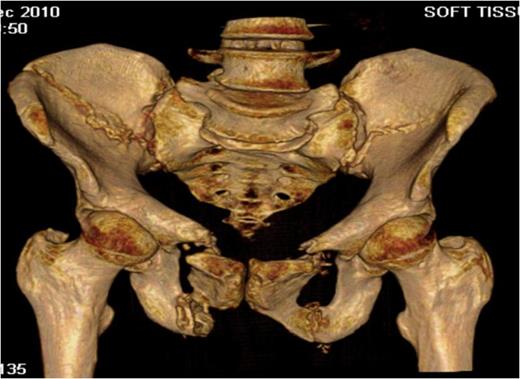

Post-operative recovery was uneventful. Bone and soft tissue biopsies showed no abnormalities. She was kept non weight bearing for 12 weeks. Subsequent dual energy X-ray absorptiometry scanning revealed mild osteopenia for which she is being managed medically. She began full weight bearing at 3 months post surgery. Final follow-up at 16 months demonstrated that the fractures had healed, and the patient was pain free and mobilising unaided (Fig. 3 & 4).

Outlet radiographs at 16 months post surgery demonstrating solid fixation and bony healing